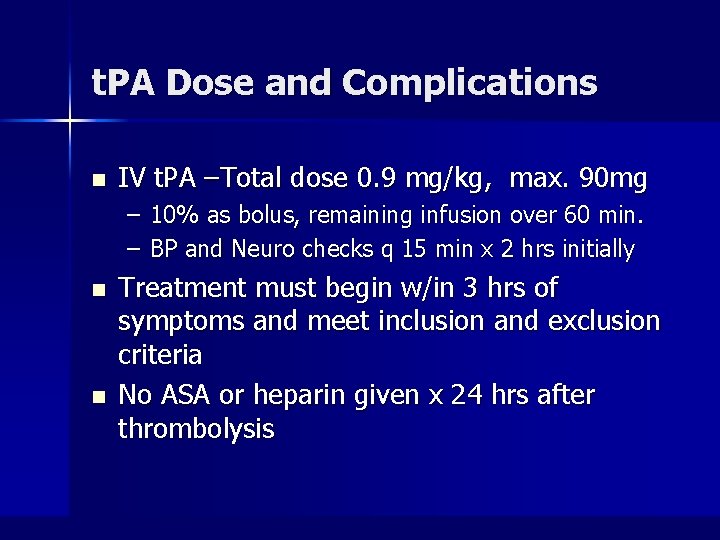

t. PA Dose and Complications n IV t. PA –Total dose 0. 9 mg/kg, max. 90 mg – 10% as bolus, remaining infusion over 60 min. – BP and Neuro checks q 15 min x 2 hrs initially n n Treatment must begin w/in 3 hrs of symptoms and meet inclusion and exclusion criteria No ASA or heparin given x 24 hrs after thrombolysis